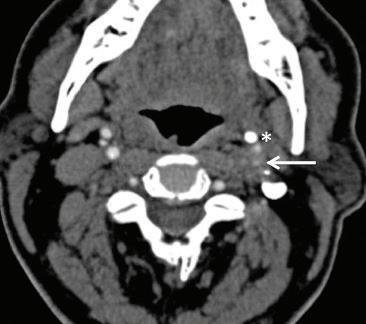

Eagle syndrome: Transient ischemic attack and subsequent carotid dissection

A 62-year-old man initially presented to our institution 3 months before his final diagnosis with transient right-sided weakness and brief loss of consciousness after reaching across his body in the shower. His medical history was significant for hypertrophic cardiomyopathy and atrial fibrillation. He had an implantable cardiac device and was on lifelong anticoagulation. Head computed tomography (CT) and CT angiography (CTA) were unremarkable, and although a transient ischemic attack (TIA) was thought to be unlikely given the anticoagulation therapy, this was a working diagnosis based on his symptoms, which were otherwise unexplained, and he was sent home.

The patient returned 3 months later with sudden-onset behavioral changes, disorganized speech, and right-sided weakness. He reported no specific activity related to symptoms. CTA demonstrated complete left internal carotid occlusion at the level of the styloid tip, 1-cm cranial to the bifurcation, which extended to the carotid terminus (figure 1). Review of imaging obtained at his presentation 3 months earlier demonstrated a normal carotid.

CT of the head obtained at the most recent visit demonstrated new anterior, middle, and posterior circulation infarcts. In addition, we observed not only that his left styloid process was elongated (3.0 cm), but also that his stylohyoid ligament was calcified to the hyoid and possibly fractured (figure 2). We speculate that the fracture might have acted as a lead-point, causing injury

and subsequent dissection of the patient’s carotid. The contralateral styloid process was within normal limits, but the ligament was also calcified.

Prophylactic contralateral styloidectomy was considered, but the patient was deemed a poor surgical candidate given his underlying cardiomyopathy and anticoagulation. After further review of imaging, we felt his right carotid was a safe distance from the right styloid and ligament. As the left carotid was occluded to the skull base, he was not offered revascularization. We speculate that our patient’s initial presentation

A B

Figure 1. A: 3-D reconstruction of the patient’s CTA with soft-tissue subtraction demonstrates the elongated and calcified stylohyoid ligament and dissected carotid artery cranial to the ligament (arrow). B: Additional 3-D reconstruction of the CTA with bone and soft tissue removed further demonstrates the dissected left internal carotid artery (arrow).

might have been a harbinger of his impending cerebrovascular accident.

Eagle Syndrome is an uncommon but well-described entity with a nonspecific clinical presentation; more benign manifestations include globus sensation, dysphagia, facial neuralgias, throat pain, and cranial neuropathies, for which a differential is extensive.1,2 In the presence of an elongated styloid bone or stylohyoid, diagnostic consideration is often given to Eagle syndrome, but it may have a more insidious presentation. Elongation of the styloid also has been reported as a cause for symptomatic carotid disease, including TIA, Horner syndrome, eye pain, and cluster headache.3 Dissection associated with elongated styloids has been reported in the neurology literature,4 but to the best of our knowledge, no prior reports have demonstrated TIA with a normal carotid and subsequent carotid dissection during two separate clinical presentations.